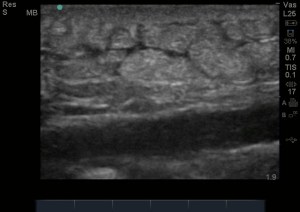

Cellulitis by bedside ultrasound looks like a bunch of rocks bunched up next to each other – termed the cobblestoning appearance of cellulitis without movement in between. If there is an abscess, this pressure will make the pus within the tissue move around, which helps in diagnosing an abscess – We call it Pus-stalsis. If there are loculations, it can easily be mistaken for cellulitis as the loculations will have echogenicity (brightness) and may look like cobblestoning, but instead, loculations are more of a cluster of grapes appearance with small movements of pus in between the loculations.

The images below shows the cobblestoning appearance of cellulitis.